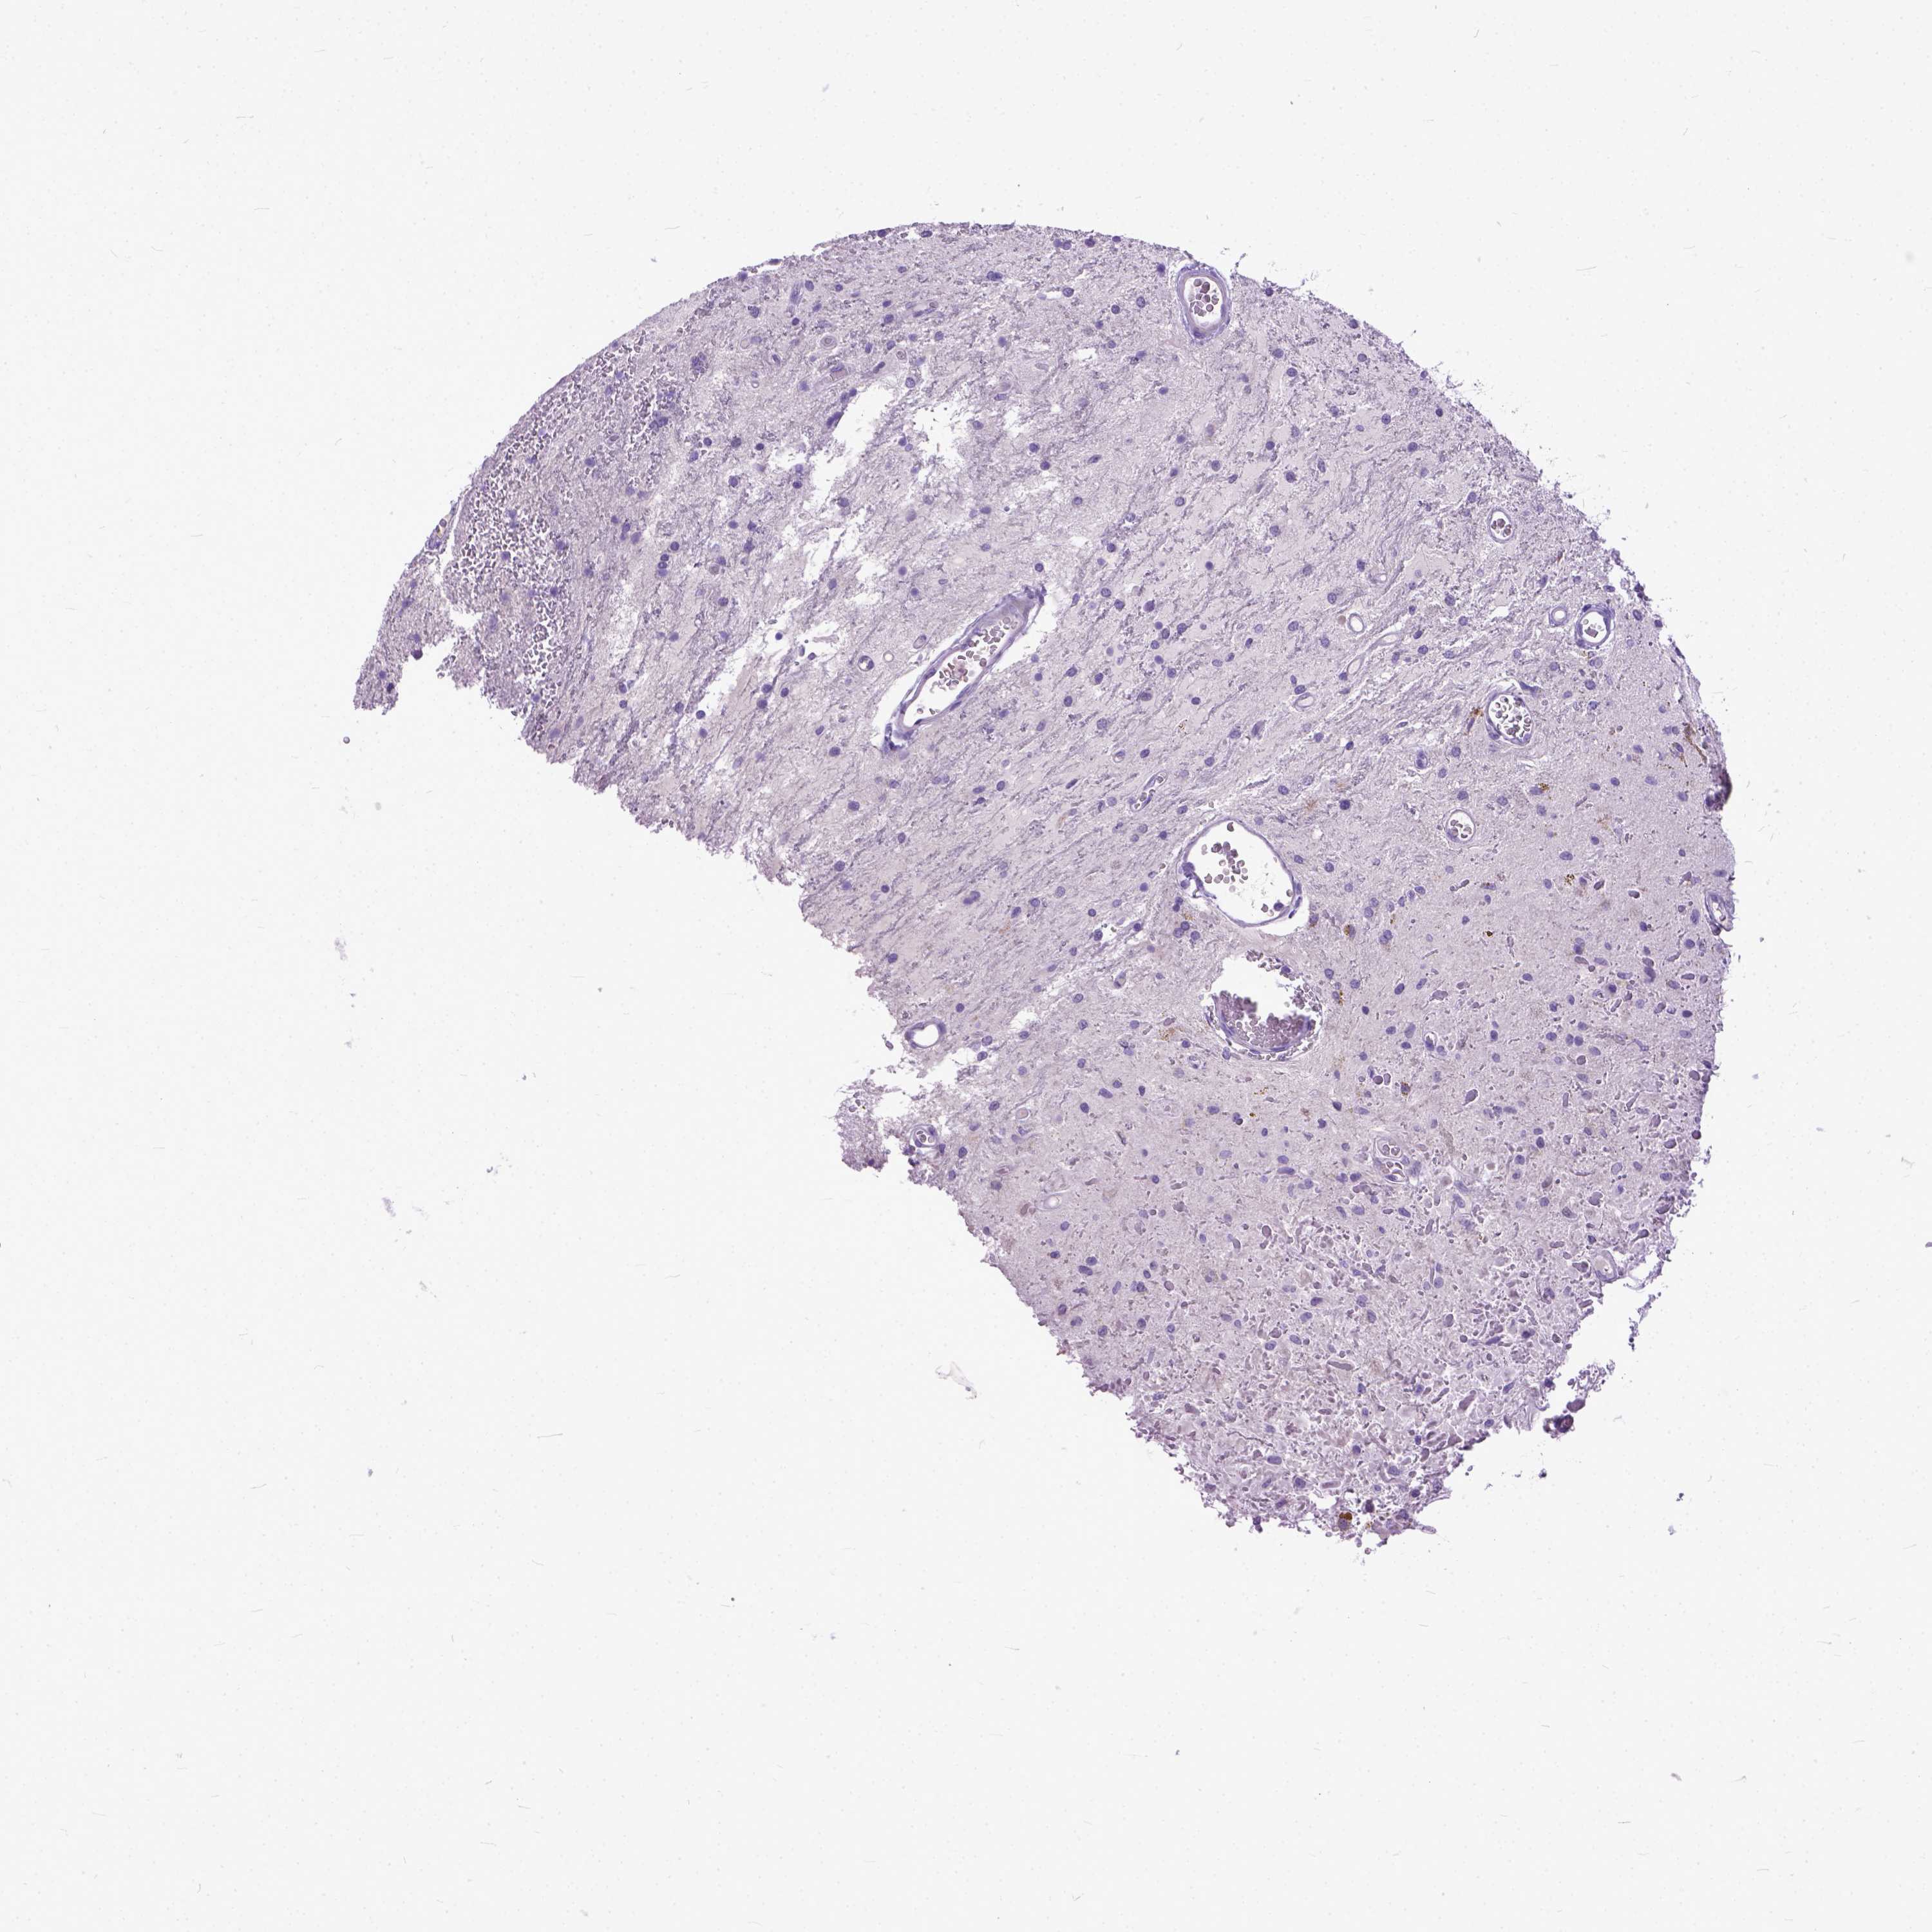

GLIOMA - Protein expressioni

A mouse-over function shows sample information and annotation data. Click on an image to view it in a full screen mode. Samples can be filtered based on level of antibody staining by selecting one or several of the following categories: high, medium, low and not detected. The assay and annotation is described here.

Note that samples used for immunohistochemistry by the Human Protein Atlas do not correspond to samples in the TCGA dataset.

Antibody stainingi

Antibody staining in the annotated cell types in the current human tissue is reported as not detected, low, medium, or high, based on conventional immunohistochemistry profiling in selected tissues. This score is based on the combination of the staining intensity and fraction of stained cells.

Each image is clickable and will lead to virtual microscopy that enables deeper exploration of all samples and also displays staining intensity scores, fraction scores and subcellular localization as well as patient and tissue information for each sample.

Antibody HPA035024

Staining

High

Medium

Low

Not detected

Intensity

Strong

Moderate

Weak

Negative

Quantity

>75%

75%-25%

<25%

None

Location

Nuclear

Cytoplasmic/membranous

Cytoplasmic/membranous,nuclear

Glioma, malignant, Low grade

Glioma, malignant, High grade